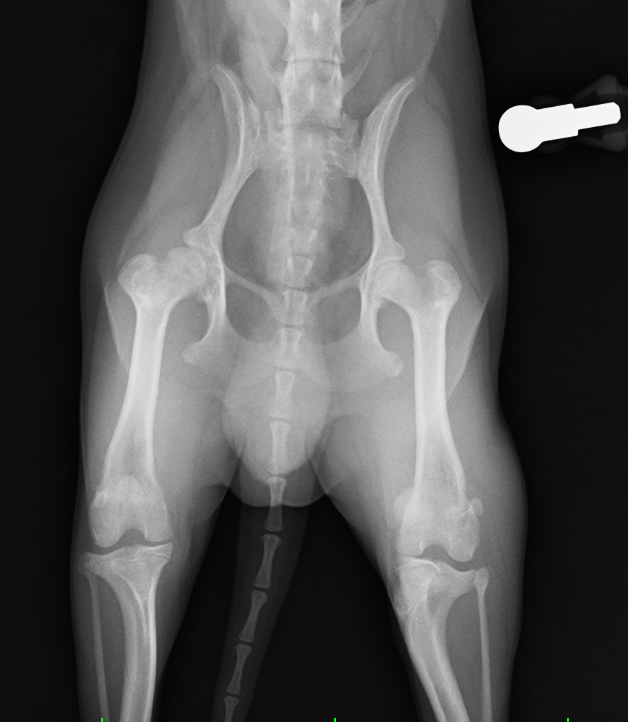

犬

整形外科

大腿骨頭壊死

大腿骨頭壊死とは?

大腿骨頭への血流不全により壊死、変形する病気で、主に若齢の小型犬に多い

症例紹介

犬種

年齢

9ヶ月齢

体重

2.4kg

性別

雄・雌(去勢済/避妊済)

来院のきっかけ

1ヶ月前より右後肢破行・挙上

所見

右後肢大腿骨頭切除

before

after